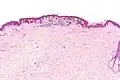

| Micrograph of a dysplastic nevus showing the characteristic rete ridge bridging, shouldering, and lamellar fibrosis. H&E stain. | |